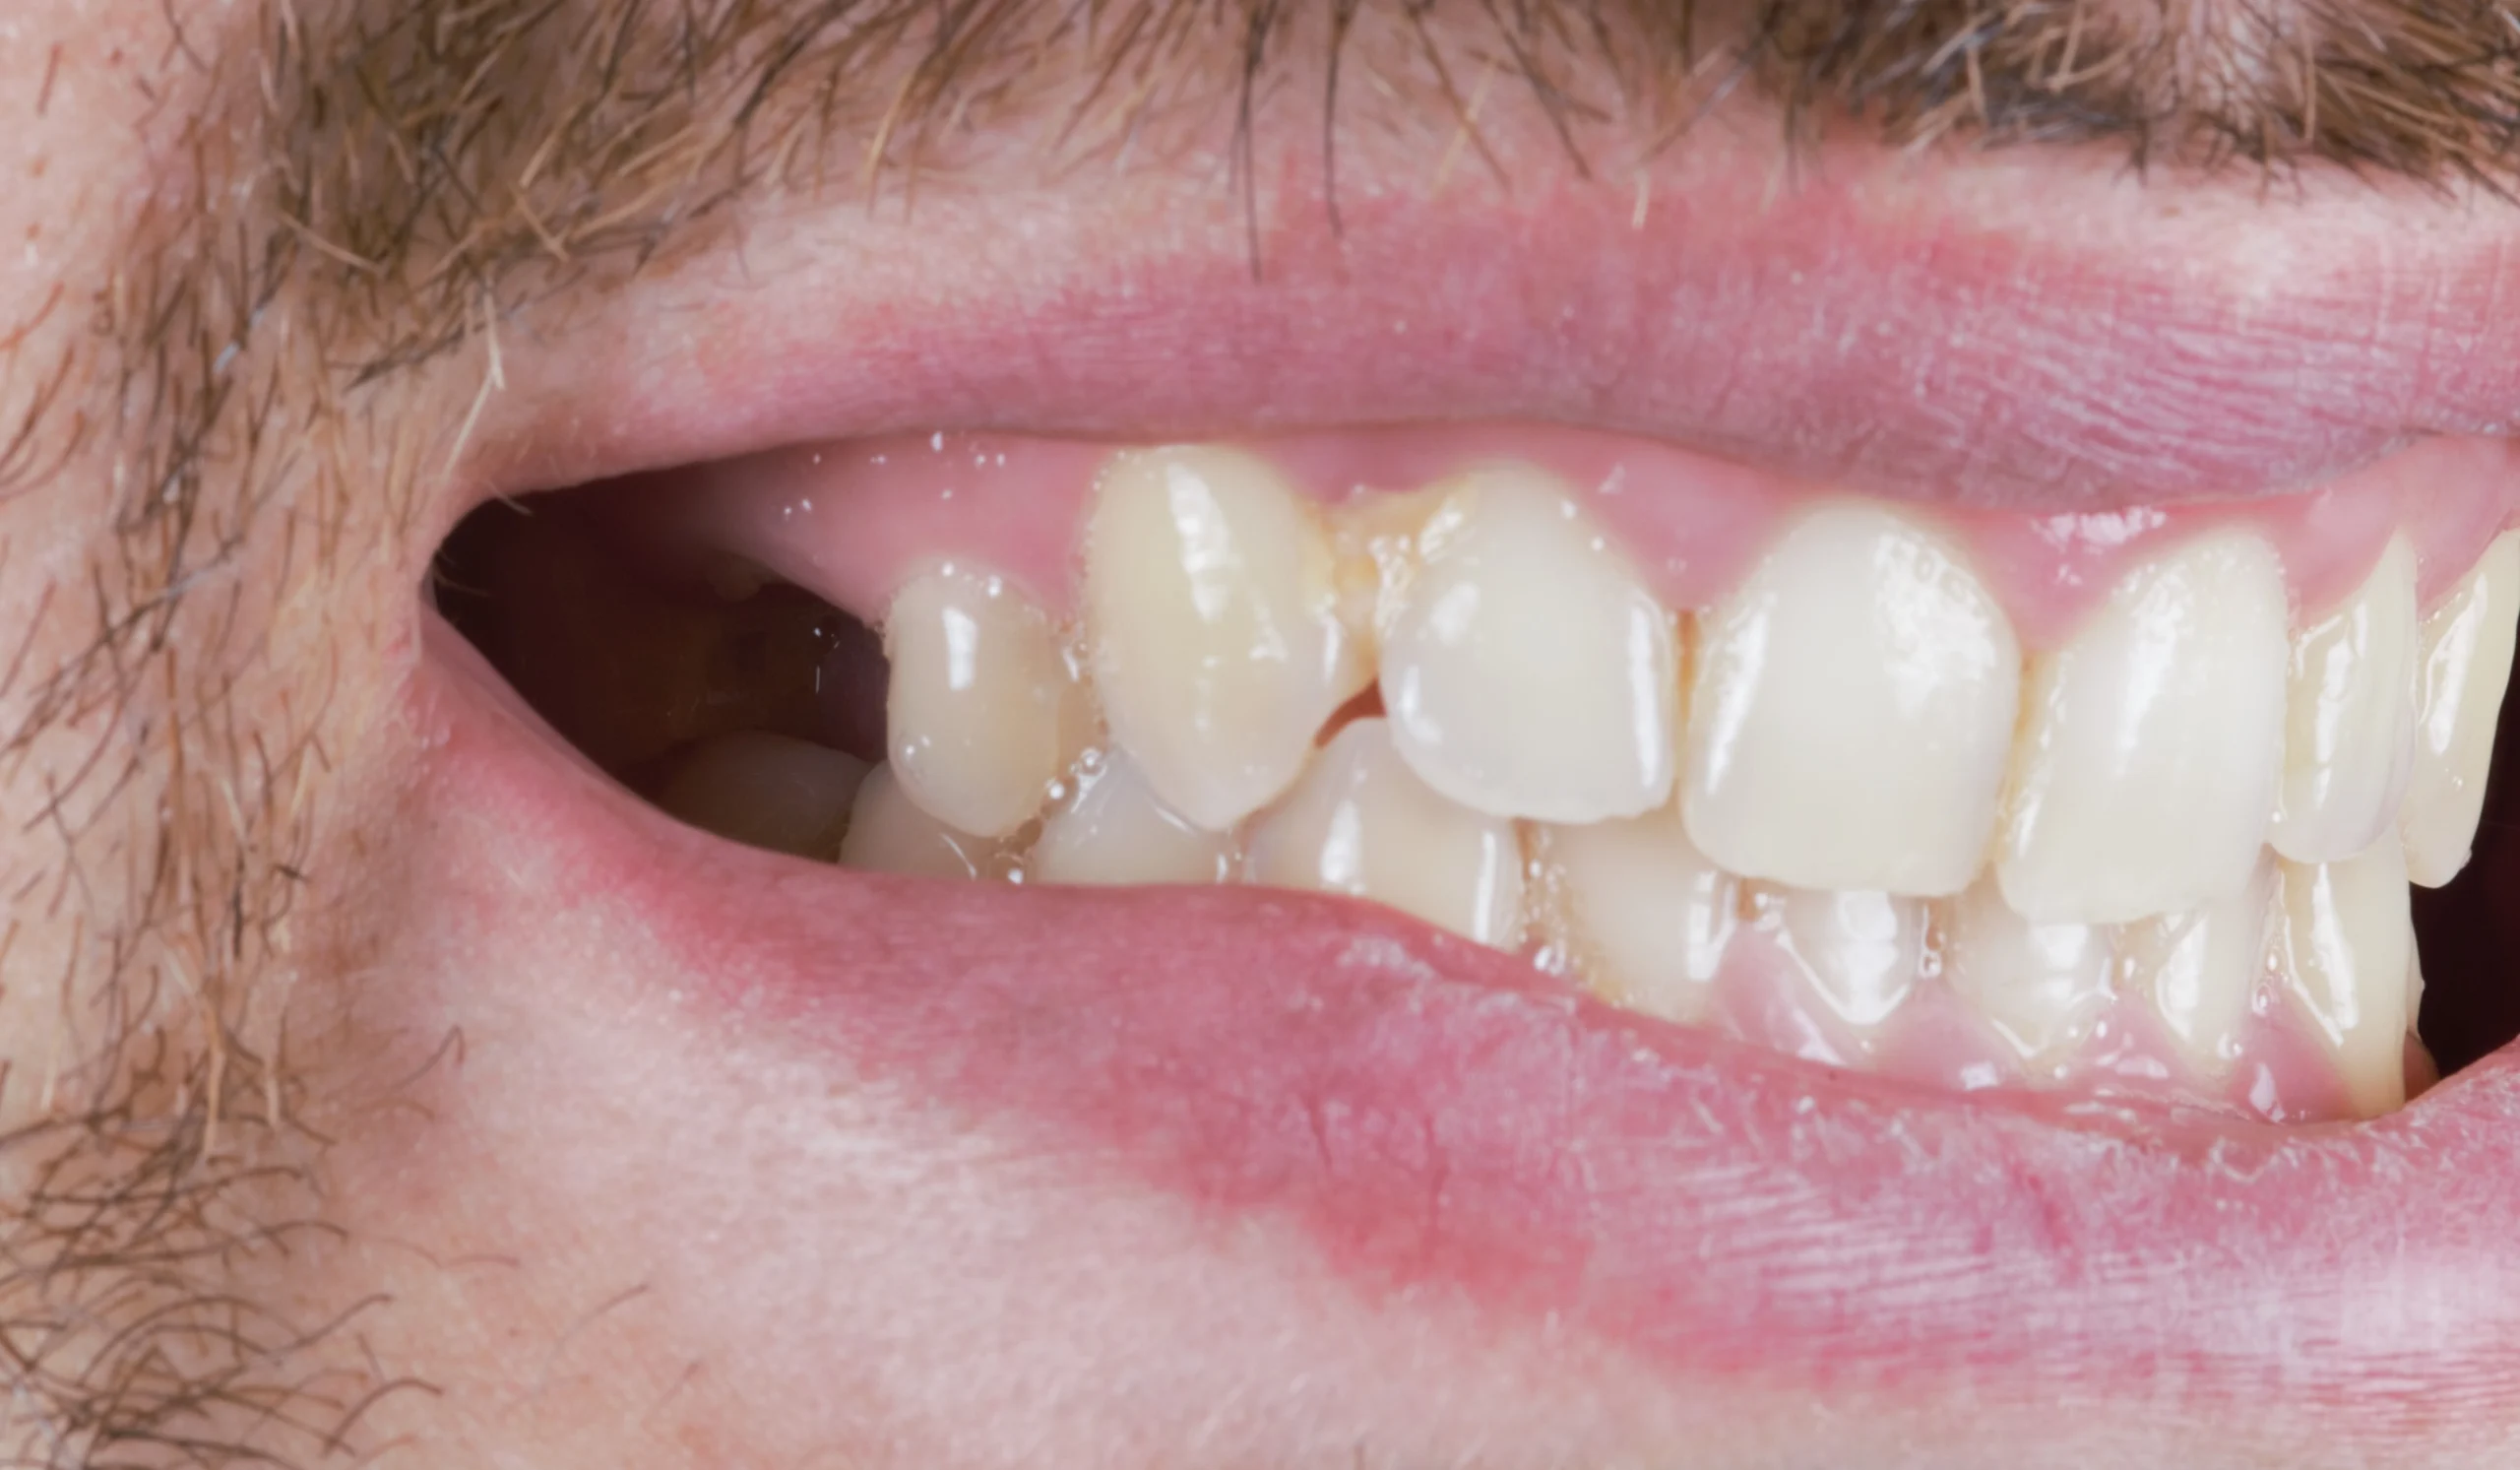

Using a computer-aided surgical guide, we performed a precise extraction and immediately placed the implant in the ideal position. Right after the intervention, the patient was provided with a temporary tooth, maintaining both appearance and comfort during the healing phase.

After a healing period of six months, the implant achieved excellent osseointegration. At this stage, we proceeded with the final restoration phase, ensuring everything was perfectly stable and ready.

We delivered a high-quality, screw-retained zirconia crown that blends seamlessly with the natural teeth. The result is a subtle yet powerful transformation—a small change that made a big difference in the patient’s smile and confidence.Â